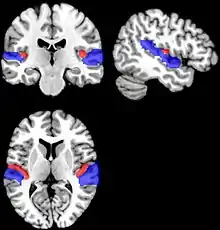

As brain regions particularly crucial in speech production are disconnected, it may cause persistent dysfluency. If the dysfluency continues into adulthood, researchers have found the basal ganglia and the attrition of white matter below the sensorimotor cortex in the brain as contributing factors.[15] In addition, because connections between the motor cortex and the basal ganglia are essential for speech production, dysfunctions in this area could be a cause of persistent developmental stuttering (PDS). PDS is the persistence of stuttering and other dysfluencies into adulthood. Researchers have proposed therapies to assist in speech production improvement, such as fluency shaping therapy.[15]

Adulthood stuttering is diagnosed as Persistent Developmental Stuttering (PDE). PDE patients can also express more external movements such as tic-like involuntary movements that non-PDE patients would not exhibit.[15] PDE patients vary in when their stuttering symptoms began, ranging from early childhood (ages 3-4) to later childhood. To treat PDE, patients can undergo fluency shaping therapy that has proven effective.[15]

15. 1 2 3 4 Giraud, Anne-Lise; Neumann, Katrin; Bachoud-Levi, Anne-Catherine; von Gudenberg, Alexander W.; Euler, Harald A.; Lanfermann, Heinrich; Preibisch, Christine (2008-02-01). "Severity of dysfluency correlates with basal ganglia activity in persistent developmental stuttering". Brain and Language. 104 (2): 190–199. doi:10.1016/j.bandl.2007.04.005. ISSN 0093-934X. PMID 17531310. S2CID 18712557.